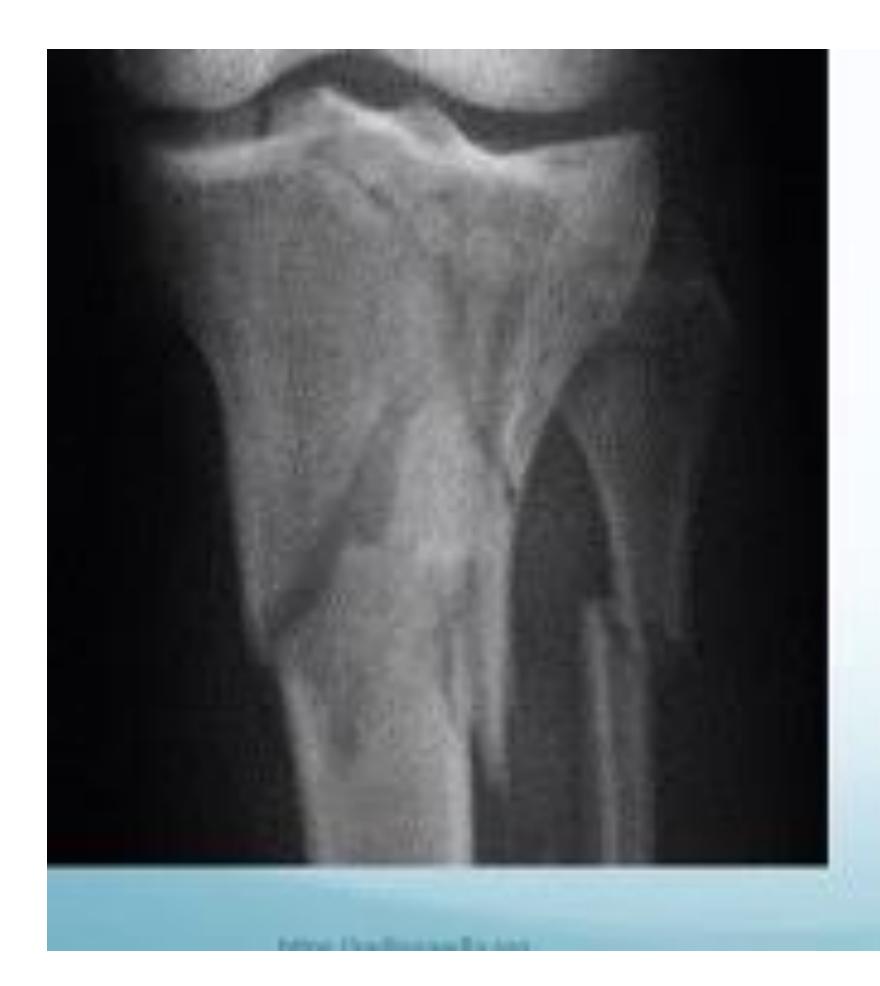

Clinical Cases:

-

14-year-old patient with pain and swelling at lower right thigh

- Most important X-ray findings: Sun ray appearance, Codmanโs triangle

- Diagnosis: Osteosarcoma

14-year-old patient complaining of pain and swelling at lower R thigh

- Findings: Codmanโs triangle, Sun burst appearance

Codman trinagle